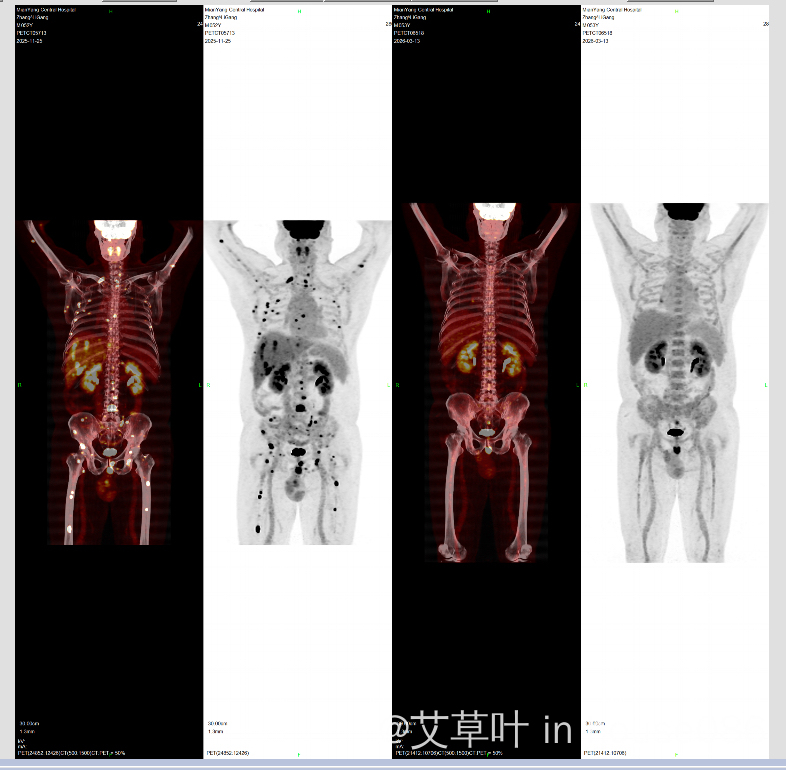

下岗夫妻需求帮助,大B继发中枢转移,有没有CaRT资源,万谢!

丈夫弥漫大B淋巴瘤、累及中枢,做了5次化疗、身体受损严重、第六次强化疗不敢做、也害怕做干细胞移植,有没有临床cart的资源啊、千恩万谢